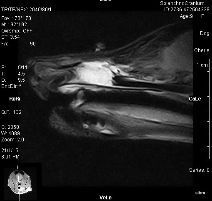

Magnetická rezonancia nám slúži aj na zobrazenie orgánov brucha a panvy a jednotlivých kĺbov končatín. Skúsený veterinárny lekár indikuje použitie magnetickej rezonancie v prípadoch, kedy nie sú dostatočné iné možnosti zobrazenia alebo diagnostiky, v iných prípadoch dá prednosť diagnostickej i terapeutickej metóde, ktorá môže byť v danom prípade špecifickejšia, napr. artroskopia kĺbov.